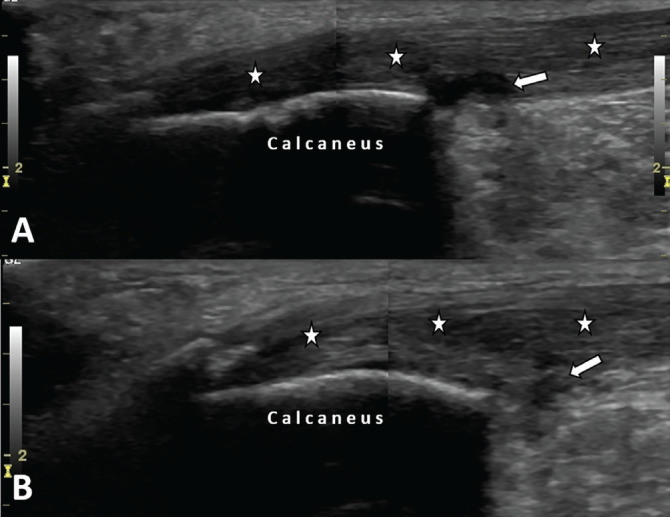

Aromatase Inhibitor-Related Lower Limb Tendinopathies: Ultrasound is on the Agenda.